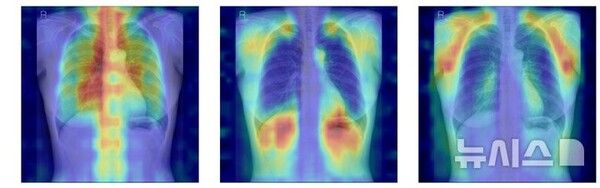

AI는 입력된 흉부 X선에서 척추와 늑골 같은 뼈 구조를 중심으로 특징을 추출하고, 이를 기존에 학습된 패턴과 비교해 정상(T-score ≥ -1.0), 골감소증(-2.5 < T-score < -1.0), 골다공증(T-score ≤ -2.5) 중 어떤 상태와 가장 유사한지를 판단한다.

연구팀은 여기에 더해 AI가 실제로 어떤 뼈를 근거로 삼아 판단하는지까지 확인할 수 있도록 '설명 가능성' 평가 체계를 설계했다. 뼈를 모두 가린 상태에서 특정 뼈 부위를 추가해 성능이 얼마나 향상하는지 확인하는 '차단 분석 방식'과 AI의 주목 영역이 실제 뼈 위치와 얼마나 일치하는지를 계산하는 '유의성 지도 방식'(IoUbone)을 통해, AI가 임상적으로 중요한 뼈 구조를 근거로 판단하는지를 정량적으로 검증했다.

그 결과, DINOv2 모델에 LoRA 방식을 적용한 모델이 AUC(정확도) 0.93(95% CI 0.92~0.94)로 가장 높은 예측 성능을 보였다. 이 모델은 뼈 구조 활용도가 가장 높고, 주목 영역의 타당성에서도 우수해, 예측력과 설명 가능성이 균형 있게 확보된 최적 모델로 평가됐다.